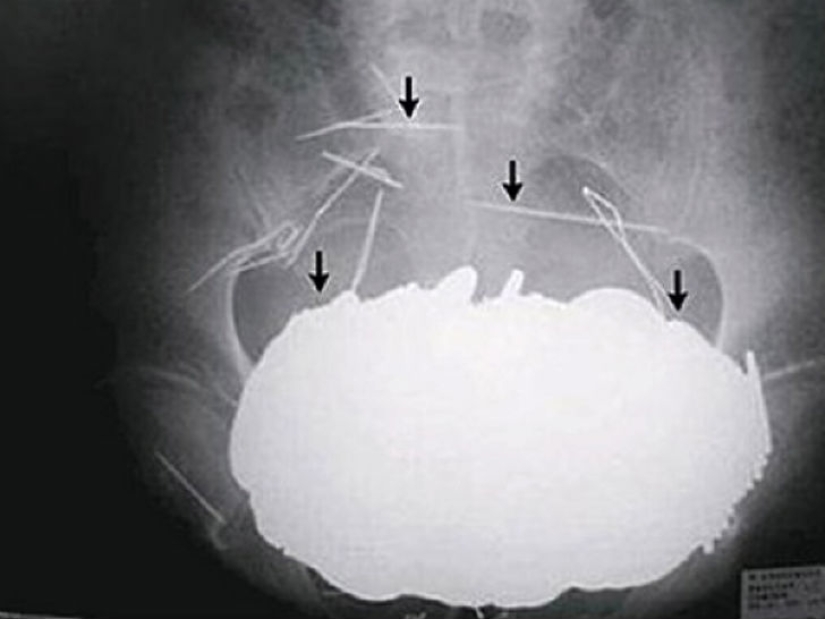

Sí, tragar cubiertos es un placer caro. ¿Qué hay de las 78 cucharas de plata que una mujer de 52 años se tragó en los Países Bajos?